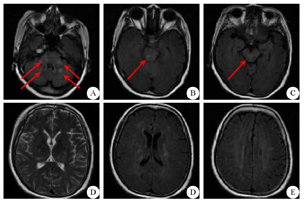

患者 女,55岁,因"畏寒发热4 d"于2017年11月13日在家人搀扶下步入中国医科大学人民医院急诊科就诊。患者发病前4 d曾有受凉发热史,体温最高达39 ℃,伴咳少量白色粘痰。既往体健,无近期疫苗接种史,否认外伤史、冶游史及自身免疫性疾病史。急诊体检:体温39.6 ℃,双肺呼吸音粗,心律齐,心率106次/min,腹部无压痛;意识清楚,颅神经未见异常,双侧巴宾斯基征阴性,颈软。肺CT扫描显示:双肺纹理紊乱,肺内散在小结节及陈旧性病变,未见明显急性炎症改变(图1A)。血液常规显示白细胞计数正常,中性粒细胞比例78.9%(↑),C反应蛋白正常。以"发热待查"收入呼吸内科住院。入院后给予头孢西丁抗炎和物理降温治疗,体温波动于38.3~41.1 ℃,并相继出现排尿、排便困难。入院1周后病情继续进展,表现为咳嗽无力、呼吸困难,以至呼吸衰竭、精神萎靡,复查肺CT显示双肺下叶模糊淡片影,右肺下叶不张可能性大,双侧胸腔积液,考虑与吸入性肺炎有关(图1B)。因患者呼吸困难继续加重,故转入ICU病房,行药物治疗的同时予以呼吸机辅助通气。期间患者体温仍持续在38 ℃以上,并反复达40 ℃,故在给予抗菌素治疗的同时又相继给予奥司他韦、更昔洛韦抗病毒治疗,并更换静脉抗菌素为万古霉素1500 mg/d、泰能4 g/d。但患者仍持续高热不退,期间多次进行血液常规化验,显示白细胞总、分数均轻度异常或正常;降钙素原0.07 ng/mL(参考值<0.05 ng/mL);肝肾功能、甲功五项、凝血功能、乙丙型肝炎、肿瘤标志物未见异常。血液病原微生物学检查:布氏杆菌、人类免疫缺陷病毒、巨细胞病毒IgM、单纯疱疹病毒IgM、军团菌IgM、柯萨奇病毒IgM均为阴性,支原体抗体滴度、肥达氏反应和外斐氏反应均无异常。免疫学检查:抗中性粒细胞胞浆抗体(-);抗核抗体谱(15项)中抗SS-A抗体(±)、抗Ro-52抗体(±);血沉、风湿三项、血IgA、IgG、IgM、IgE及血清蛋白电泳均未见明显异常。血培养:未见需氧、厌氧菌生长。痰涂片:无细菌、结核杆菌生长。尿常规、尿沉渣定量无异常。心脏超声、全腹CT扫描无异常。入院第11天(2017年11月24日)因停用镇静药物后患者仍呼之不应,急请神经内科会诊。脑脊液检查:脑脊液压力160 mmH2O(1 mmH2O=0.098 kPa),外观无色透明;脑脊液常规:白细胞总数352×106/L(↑),未见红细胞;脑脊液生化:糖2.34 mmol/L(↓)、蛋白质0.78 g/L(↑)、氯化物正常;细菌及结核杆菌涂片(-)。血液及脑脊液水通道蛋白和脑脊液寡克隆带未检测。因患者脑脊液白细胞总数增高较明显,故给予抗菌素治疗的同时给予静脉甲泼尼龙(500 mg/d、连续4 d,后逐渐减量)治疗。激素治疗的第2天患者体温开始下降,第5天降至正常,第9天自主呼吸明显恢复,但仍咳痰无力。在患者呼吸困难、发热症状好转的同时,也发现患者存在四肢瘫痪(双上肢肌力Ⅱ级、双下肢肌力Ⅰ级)。为进一步明确肢体瘫痪原因,入院4周后(2017年12月7日)行头颅MRI平扫,显示脑干、双侧丘脑、双侧小脑半球、双侧半卵圆中心、侧脑室旁及基底节区多发、不对称的异常信号(图2)。2017年12月14日颈段MRI平扫显示:延髓与颈髓交界、C1~T1节段间多发、不连续的髓内异常信号(图3)。结合患者发热、亚急性起病过程,尽管脑脊液呈炎性改变,但给予抗病毒、抗细菌治疗效果不佳,并结合中枢神经系统影像学改变,即颅内及脊髓均有受累,支持中枢神经系统脱髓鞘性疾病的诊断。2017年12月24日患者自主呼吸完全恢复,此期间排便功能及肌力也逐渐恢复,于2017年12月28日转回呼吸内科病房。出院后随访3个月,患者仍处于恢复中,双上肢肌力Ⅴ-级、双下肢肌力Ⅳ级,因遗留排尿困难仍予留置导尿管。

A:双侧小脑半球近第四脑室、双侧桥壁、延髓呈点片状T2 FLAIR高信号(箭头所示);B:脑桥(以右侧及背侧为著)呈T2 FLAIR高信号(箭头所示);C:中脑右侧大脑脚呈T2 FLAIR高信号(箭头所示);D:双侧丘脑、基底节区(以右侧内囊后肢为著)呈T2WI高信号;E:侧脑室前后角呈多发片状T2 FLAIR高信号;F:双侧半卵圆区呈多发片状T2 FLAIR高信号

ADEM病变主要累及脑和脊髓的白质,MRI对其诊断具有重要意义,一般表现为侧脑室旁及额颞顶枕白质区内多发的点片状病灶,部分可见"垂直脱鞘征";同时也可见于灰质,后者以基底节区、丘脑、脑干多见。ADEM的脑部病灶多在T1WI呈低或稍低信号,在T2WI和FLAIR呈高信号,多双侧不对称,形态可呈圆形、椭圆形或不规则,直径多为1.0~2.0 cm或略小;脊髓病灶主要位于颈、胸髓髓内,表现为连续或节段性的长条形信号,长度可达3~4个脊椎节段,T1WI上呈低信号,T2WI上呈高信号,信号多较均匀,脊髓无增粗,且无特异性[3,4]。除中枢神经系统影像学改变外,ADEM的诊断还需符合以下标准:(1)急性起病,首次因可疑中枢神经系统炎性脱髓鞘而表现出多灶性神经功能缺损;(2)排除中枢神经系统感染、结缔组织病、遗传代谢性疾病及肿瘤;(3)发病3个月后没有新的临床表现和MRI改变[1,5,6,7]。本例患者的中枢神经系统影像学改变和临床表现均符合ADEM的诊断标准,但该患者发病时无确切的局灶性神经功能缺损表现,并且其后因给予呼吸机通气并镇静也影响了对神经系统体征变化的观察,包括对呼吸衰竭、四肢瘫痪及尿潴留原因的分析不足,导致未能早期及时诊断。